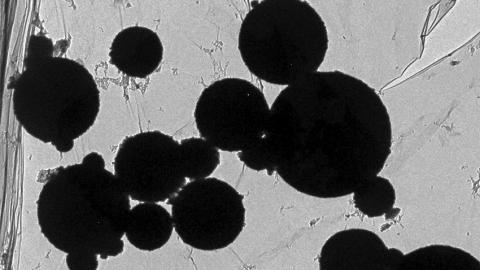

뇌 속에서 자연스럽게 생성되는 자철석은 항상 4각형이나 8각형 구조를 갖고 있다. 그러나 최근 연구 결과 시신들의 뇌 속에서 나노 크기의 원형체가 발견되고 있다. 연구자들은 또한 뇌물질 속에서 또 다른 금속성 나노입자들을 찾아냈다.

플래티늄, 니켈, 코발드 등 예기치 못한 입자들을 발견했는데 자석철을 포함한 이런 물질들은 뇌속에 공기오염 물질이 다량 유입되고 있다는 것을 말해주는 것이다. 마허 교수는 자석철을 포함 모든 물질들이 다각형이 아닌 원형 구조였다고 설명하고 있다.

고온에서 형성된 물질임을 말해주고 있다는 것. 교수는 “이런 물질들이 인체 내 낮은 온도 속에서 만들어진 것이 아니라 고온의 불 속에서 화학적 연소가 일어나면서 발생한 나노 원형체일 가능성이 매우 높다“고 말했다.

발전소, 공장, 자동차 엔진, 더 나아가 자동차 브레이크에서 마찰가열을 통해 발생하는 오염물질들의 형상과 일치하고 있다는 주장했다. 분석 중인 입자들을 보면 지름이 150나노미터(10억분의 1m) 이하인 것으로 나타나고 있다.